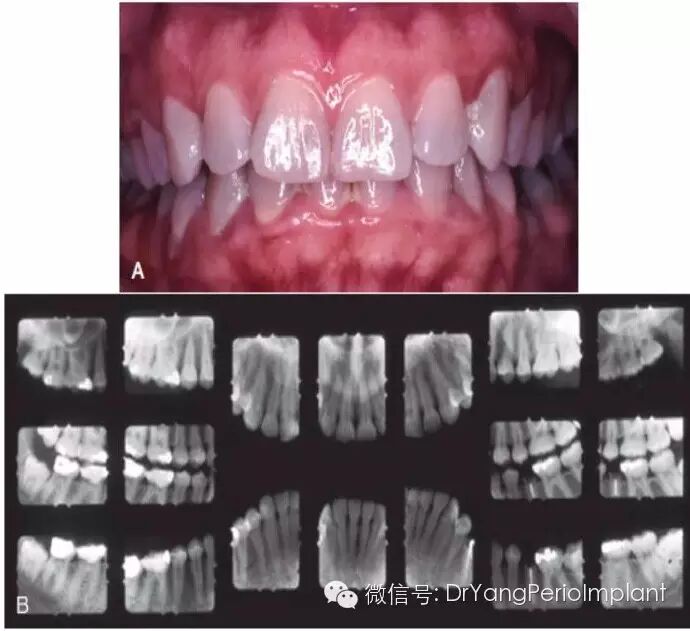

圖片顯示牙齦炎症,臨床檢查未發現臨床附著丟失,X光未見骨吸收。圖片顯示明顯的菌斑牙石,牙齦紅腫)。(圖片取自Carranza Clinical Periodontology 2012, 11版)